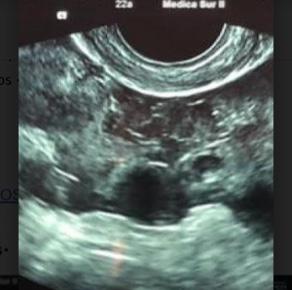

Mujer de 22 años, primigesta, sin antecedentes de importancia, quien acude a la consulta externa de ginecología por presentar dolor abdominal de moderada intensidad de inicio súbito acompañado de nausea y vómito. Previo a este cuadro refiere sangrado menstrual hace un mes y continuar con leve sangrado intermitente, así como ingesta de pastillas de emergencia a dosis de 1.5 mg entre 5-6 semanas previas al inicio de los síntomas sin especificar fecha exacta. Niega prueba de embarazo ni otros estudios de diagnóstico. A la exploración física se encuentran signos vitales dentro de parámetros normales, con dolor abdominal localizado en la fosa iliaca izquierda con rebote positivo y signos de irritación peritoneal, al tacto vaginal se evidencia escaso sangrado transvaginal, con cérvix posterior cerrado. Se realiza ultrasonido transvaginal encontrando el útero en anteversión, con medidas de 7.5 x 4.2 x 5.7 cm, endometrio heterogéneo con grosor de 19.1 mm, sin evidencia de saco gestacional intrauterino; ovario izquierdo con imagen quística compleja, imagen anecoica ecogénica que muestra vascularidad periférica a la exploración Doppler color, el ovario derecho no se delimita parcialmente definido con heterogeneidad del anexo, con presencia de abundante líquido libre en fondo de saco posterior con ecos internos que sugieren material hemático.(figuras 1-2)

Figura 2. Anexo izquierdo con imagen quística compleja.

Figura 1. Liquido libre en fondo de saco posterior.